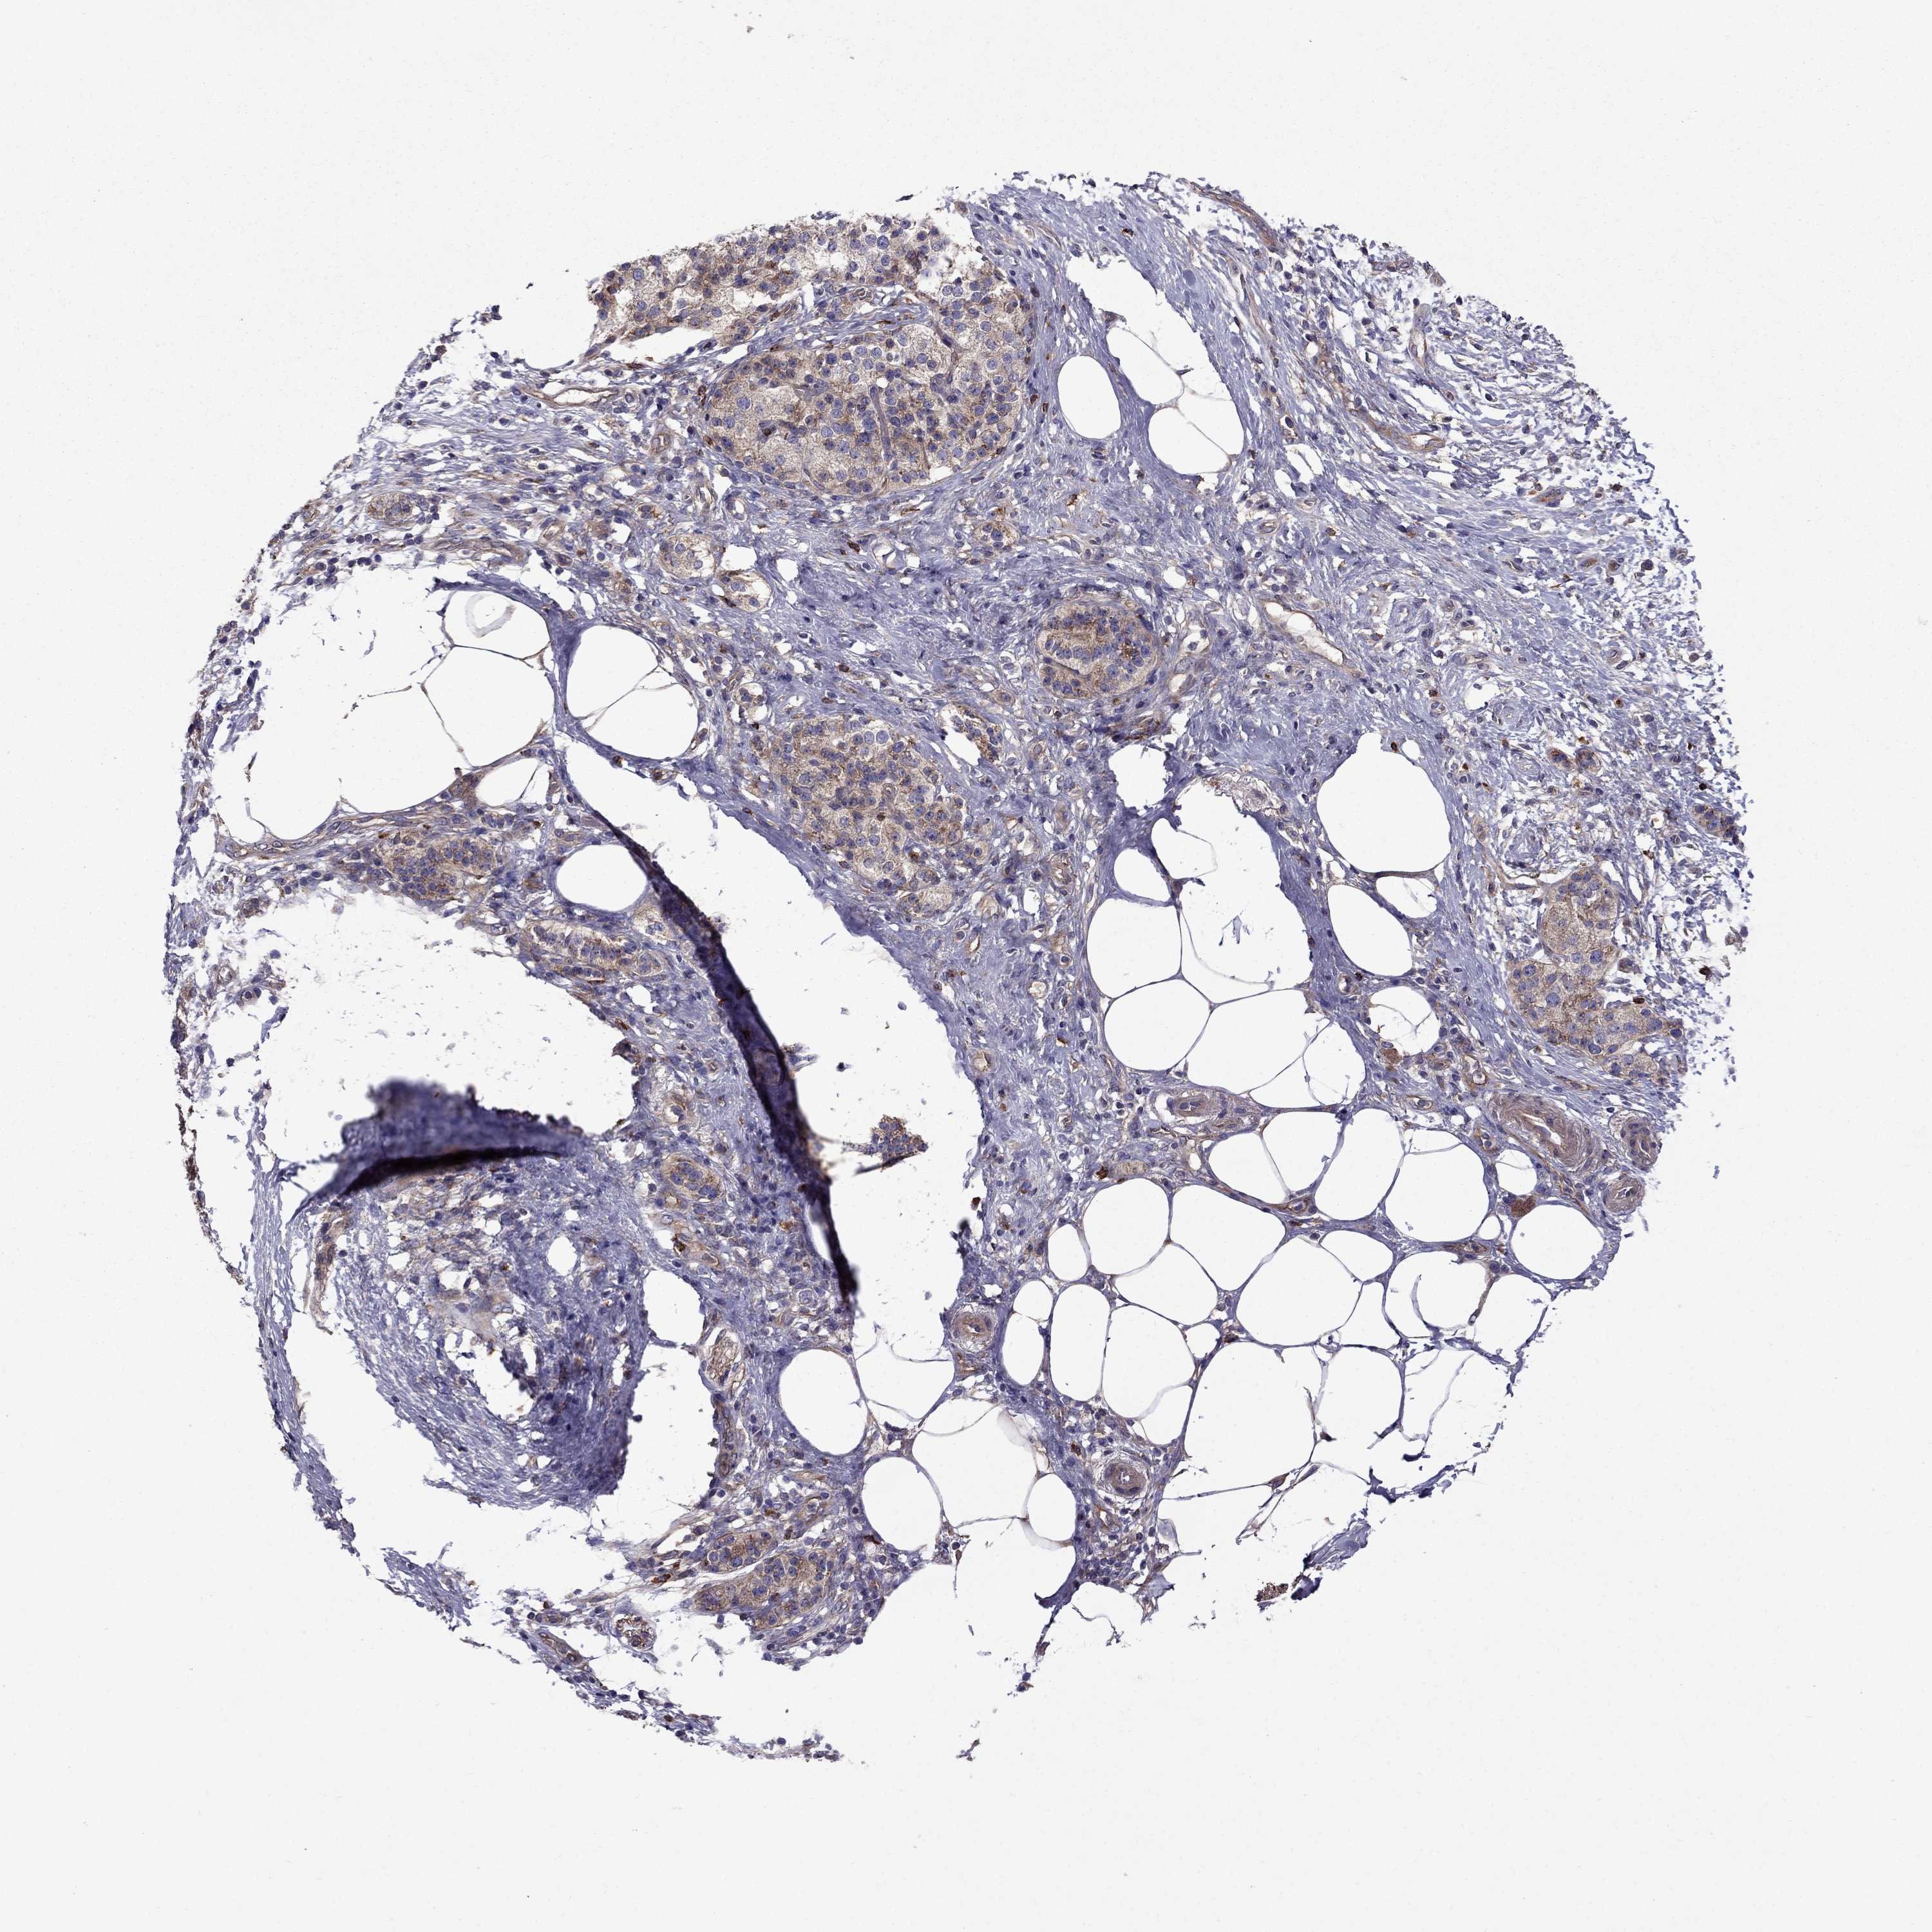

PANCREATIC CANCER - Protein expressioni

A mouse-over function shows sample information and annotation data. Click on an image to view it in a full screen mode. Samples can be filtered based on level of antibody staining by selecting one or several of the following categories: high, medium, low and not detected. The assay and annotation is described here.

Note that samples used for immunohistochemistry by the Human Protein Atlas do not correspond to samples in the TCGA dataset.

Antibody stainingi

Antibody staining in the annotated cell types in the current human tissue is reported as not detected, low, medium, or high, based on conventional immunohistochemistry profiling in selected tissues. This score is based on the combination of the staining intensity and fraction of stained cells.

Each image is clickable and will lead to virtual microscopy that enables deeper exploration of all samples and also displays staining intensity scores, fraction scores and subcellular localization as well as patient and tissue information for each sample.

Antibody HPA059297

Antibody HPA069003

Antibody CAB003434